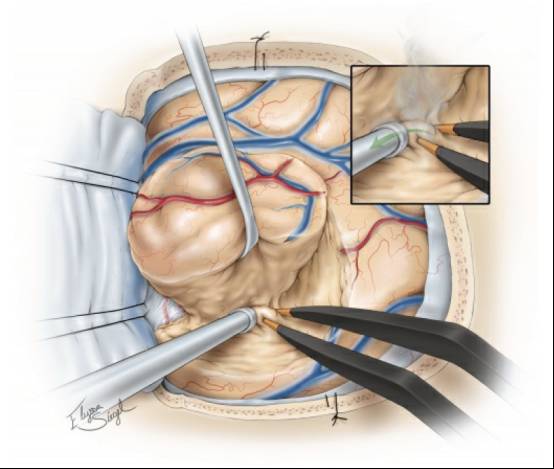

图4. 硬脑膜可采取曲线或放射状的方式打开。充分暴露肿瘤与周围正常脑皮质区域。外观相对正常的皮质常覆盖肿瘤的边缘。

在发生脑移位之前(由肿瘤内减压和/或脑脊液释放引起),笔者会根据导航,用丝线标记肿瘤的边缘。详细检查脑表面会发现,病灶累及的脑回会扩大,变色和血管减少。如果有必要,皮层电刺激可以精确定位功能区的界限。周围的大静脉和动脉要识别和保留。

图6. 首先用软脑膜下电凝痕迹标记浅表的肿瘤边缘并电凝肿瘤表面的血管。保护过路的皮质动脉和静脉。将一块肿瘤组织进行组织学检查并确认术前诊断。

一些低级别胶质瘤边缘呈浸润性,很难完全划定肿瘤与周围正常/有功能组织的界线,而另一些可以明确划出界线。换句话说,一些低级别胶质瘤是灰色的,柔软的,可以被抽吸,并有不同的质地;这些特点大大方便肉眼完全切除。而另一些肿瘤相对纤维化和异质性使得切除变得复杂,因为术者没有可靠的方法来区分肿瘤与瘤周组织。

图7. 笔者常常借助肿瘤组织的一致性特点和术中导航环形离断肿瘤。如果可能的话尝试整块切除肿瘤。中央部分切除会导致导航精度会大大降低。更重要的是,整块切除肿瘤能够提高手术效率,减少失血,使操作者保持沿肿瘤边缘的平面将其切除。在肿瘤的内部和外围同时操作会导致肿瘤边缘混乱不清。.

胶质瘤的白质剥离和分离技术值得特别重视。双极反复钳取并电凝肿瘤的假包膜,这种逐步的操作能够乳化假包膜并使其与瘤周的水肿组织分离。接下来,用吸引器吸除该乳化物,继续暴露下一层假包膜并进一步电凝和分离。

该技术将分离和电凝同步完成。换言之,是将双极电凝当成肿瘤剪刀一样使用,

注意在双极电凝头端持续冲水。(上图,图7插图)。